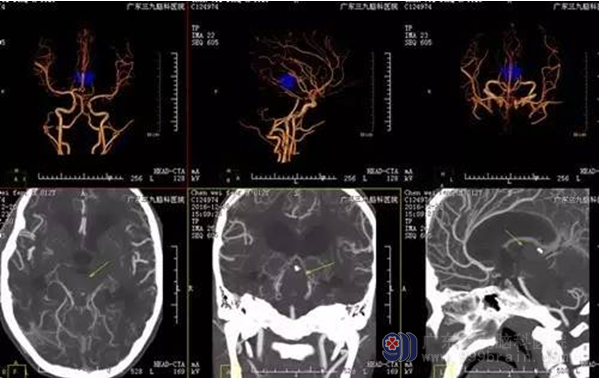

术前CTA提示病变周围血管包绕,血供丰富